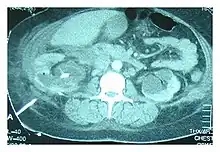

CT scan showing nephrostomy tube, indicated by the white line on the bottom left, in a case of urinothorax being treated

Abdominal ultrasonography and CT scan can help diagnose the underlying condition of the genitourinary tract. If other methods prove inconclusive, an accurate diagnosis can be made by a technetium-99m kidney scan, which shows albumin labeled with 99Tc that translocates into the pleural space from the genitourinary tract.[4]